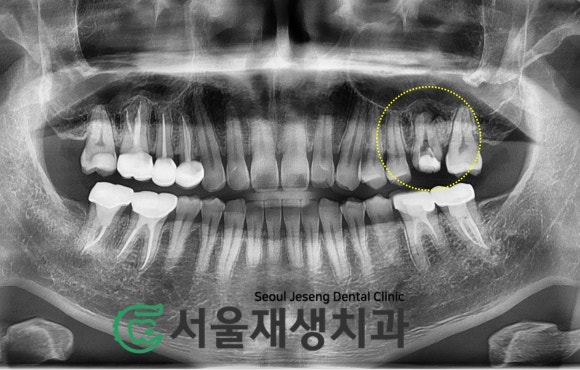

사진 속 노란 동그라미를 주목해주세요.

한창 신경치료 중인 어금니가 하나 보입니다.

이미 재신경치료를 했는데도

여전히 아파요!!!